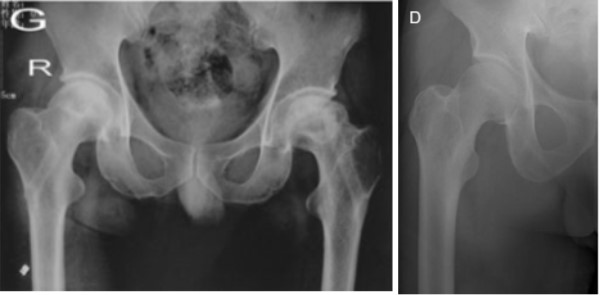

● 股骨头I、II期坏死3.提供足够的力学支撑,防止股骨头塌陷